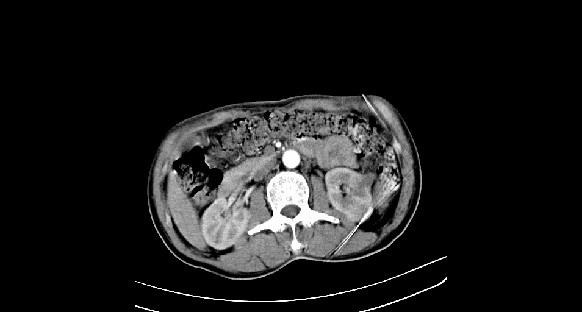

男性,70岁,体检b超发现左肾占位,请各位战友发表一下观点

左肾有两个病灶,且较大的病灶内可见点状钙化灶,增强扫描边缘也是呈渐进性强化,中央部分未见明显强化